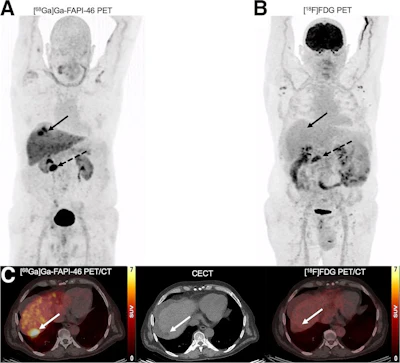

A 65-y-old man with HCC and liver cirrhosis confirmed by MRI. Ga-68 FAPI-46 PET/CT demonstrates increased focal uptake (SUVmax, 13.26, and TBRmax, 2.89) in liver, whereas F-18 FDG-PET/CT scans showed non–F-18 FDG-avid lesion (SUVmax, 3.24, and TBRmax, 1.43), indicated by solid arrows. Additionally, histologically proven adenocarcinoma in colon transversum was identified as pathologic with Ga-68 FAPI-46 alone (dashed arrows). Journal of Nuclear Medicine